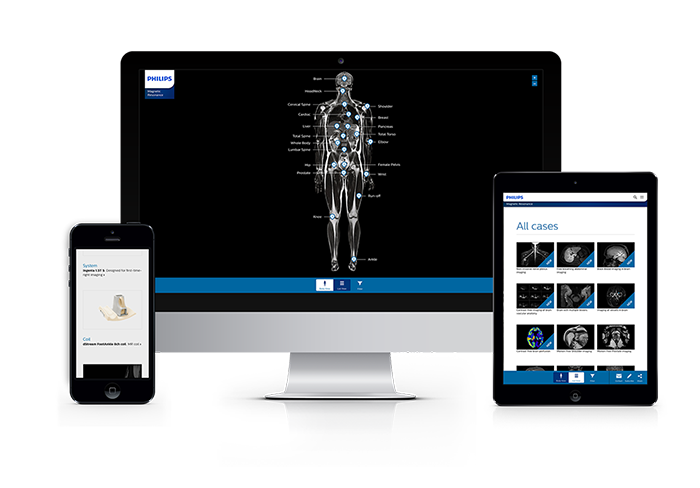

MR Body Map

Clinical cases from nearly every anatomy Explore 100+ clinical cases from your peers around the globe, that showcase how Philips MR digital technology strengthens your imaging needs.